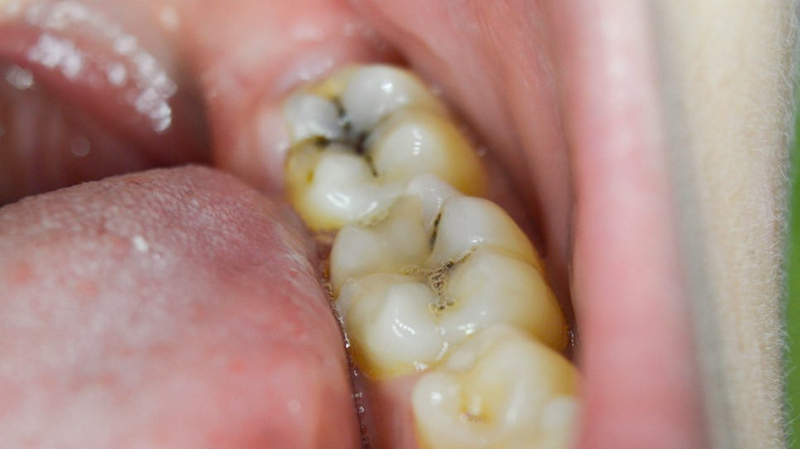

Tooth decay is one of the most common dental problems worldwide, and if not treated in time, it can lead to severe pain, infection, and even tooth loss. In this post, we’ll introduce three major treatment options: tooth fillings, dental crowns, and root canal therapy.

Cavities (dental caries) occur when bacteria produce acid that breaks down the enamel. If untreated, decay progresses deeper into the dentin and pulp, eventually requiring more complex treatments.

- When it’s used: Small to medium cavities.

- Procedure: The decayed portion is removed and filled with composite resin, ceramic, or other durable materials.